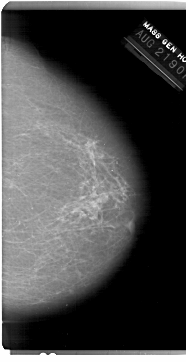

A_1215_1.LEFT_MLO

DATE_OF_STUDY 21 8 1990

PATIENT_AGE 66

FILM_TYPE REGULAR

DENSITY 2

DATE_DIGITIZED 9 7 1998

DIGITIZER HOWTEK 43.5

LEFT_MLO LINES 6871 PIXELS_PER_LINE 4021 BITS_PER_PIXEL 12 RESOLUTION 43.5 OVERLAY